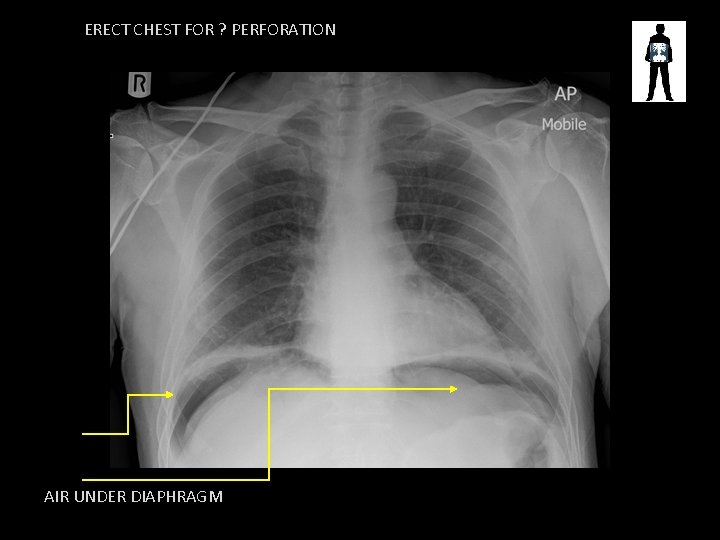

ERECT CHEST FOR ? PERFORATION AIR UNDER DIAPHRAGM